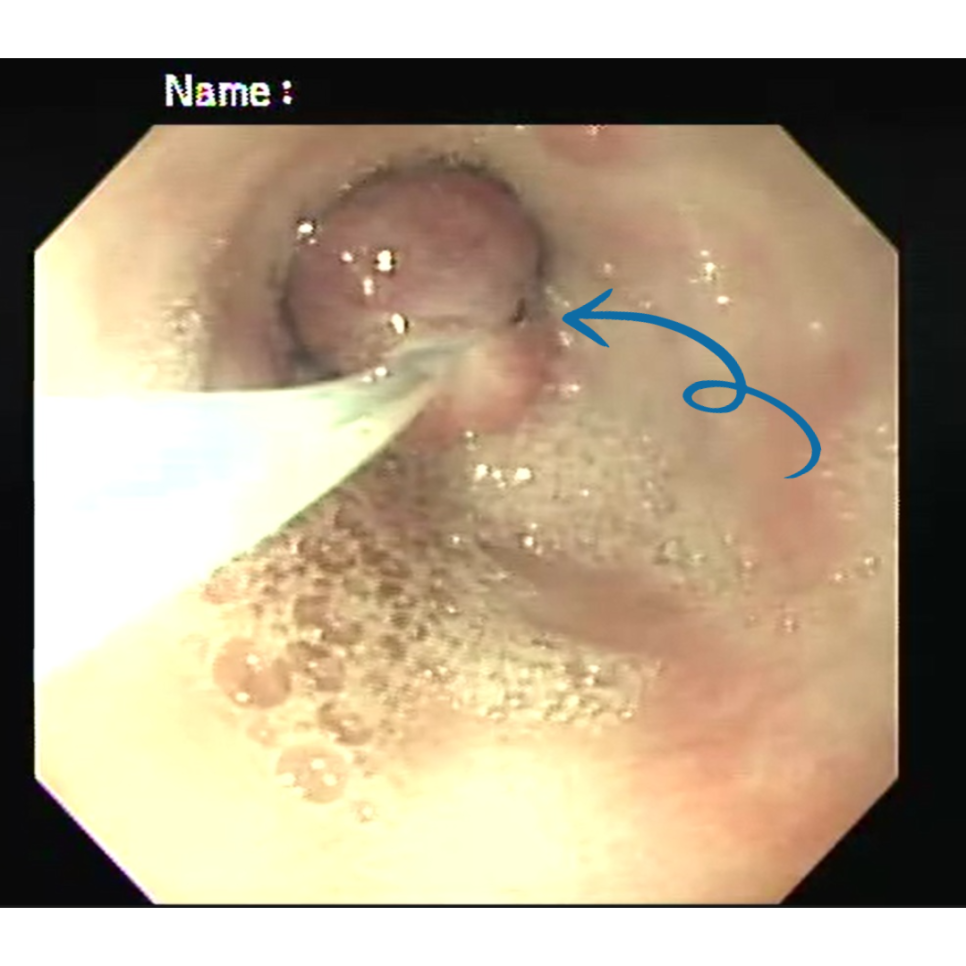

▶ 강아지 위 내시경 수술 중

▶ 내시경 폴립 제거 과정

내시경 기구를 이용해 폴립의 기저부를 확인한 후, 스네어(snare)를 이용해 병변을 안전하게 절제하였습니다.

출혈은 최소화되었으며, 제거 후 위 점막 상태도 안정적인 것을 확인하였습니다.

절제된 폴립은 조직 검사를 위해 병리 검사로 의뢰하였습니다.

▶ 강아지 위 내시경 수술 후

내시경 후 제거된 polyp입니다.